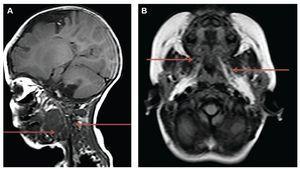

With nuclear magnetic resonance, after infiltration of pure ethanol, a moderate decrease in the volume of the lesion occupying the vascular spaces was observed along with the jaw, parapharyngeal, prevertebral, submandibular and sublingual spaces on the left side. There was also an increase in airway diameter and absence of movement that supports the efficacy and reports minimal adverse events.11 However, its use is not compared with other treatments. Other relevant publications are those of Cuervo et al.8 and Lobo et al.,12 denoting its effectiveness in uniand macrocystic hygromas. Several treatment sessions are often necessary and supplement with surgery is sometimes necessary to obtain a satisfactory result.

With regard to ethanol, Burrows et al.13 reported its use at rates of 95-98% as an aggressive sclerosing therapy because of the sudden precipitated proteins in endothelial injury. This will exceed the dose of 1 ml/kg or 60 ml and with potential side reactions such as tissue necrosis, (Fig. 5). Currently, the patient is under clinical management due to additional diseases caused by prematurity and is awaiting definitive surgical treatment.

Figure 5 Nuclear magnetic resonance of the neck and facial mass (A) and skull (B). A moderate decrease is observed in the volume of the lesion within the vascular spaces and jaw and parapharyngeal, prevertebral, submandibular and sublingual locations on the left side when compared with the previous study (arrows), mainly at the expense of cystic portions.